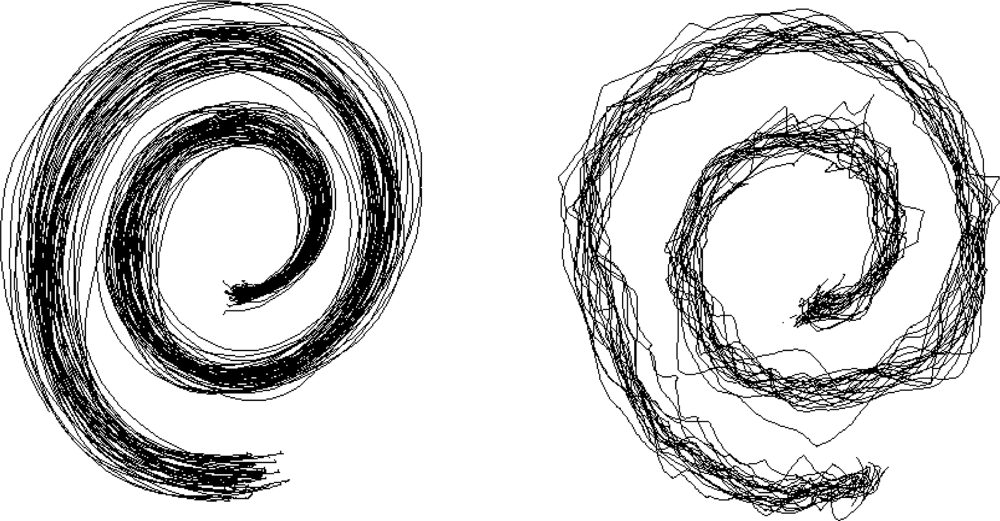

2.8. Evaluation of Handwriting and Drawing

- Miralles, F.; Tarongí, S.; Espino, A. Quantification of the drawing of an Archimedes spiral through the analysis of its digitized picture. J. Neurosci. Meth 2006, 152, 18–31. [Google Scholar]

| Analysis of writing (digitizing tablet) |